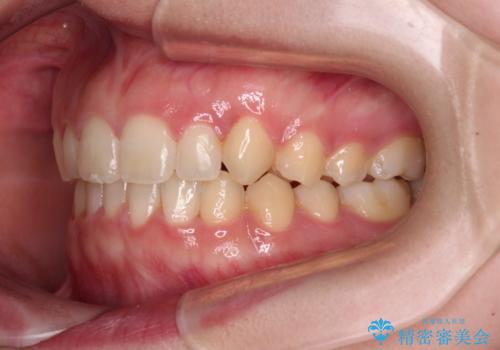

- 八重歯を気にして来院された患者様です。

八重歯のために乳歯が残存していたため、乳歯を抜去して八重歯となっている犬歯を歯列に収めることとしました。

八重歯の移動量が多くなるため、インビザラインと併用してワイヤー矯正を行い、八重歯を改善した後に、上下歯列をインビザラインで整えることとしました。

犬歯は歯根が長くて太いため移動に時間がかかる上に、周囲の歯が八重歯に寄ってきてしまうため、仕上がるまでに期間がかかりました。